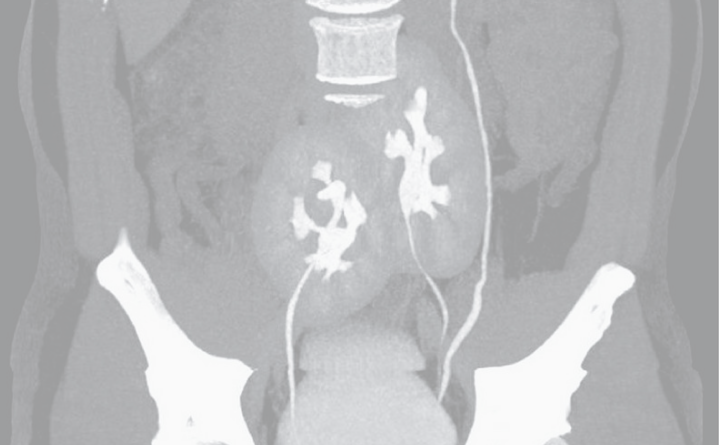

Los expertos que lo atendieron hablaron sobre el hallazgo en The New England Journal of Medicine. Al atender al paciente de 38 años para entender las causas del dolor, le realizaron una tomografía computarizada.

Para su asombro, en las imágenes encontraron que además de una hernia discal en la región lumbar, tenía también tres riñones en lugar de dos.

Uno de los riñones tenía forma y tamaño normal y estaba ubicado a la izquierda, en tanto que los otros dos estaban fusionados en forma de herradura y ubicados mucho más abajo, cerca de la zona de la pelvis.